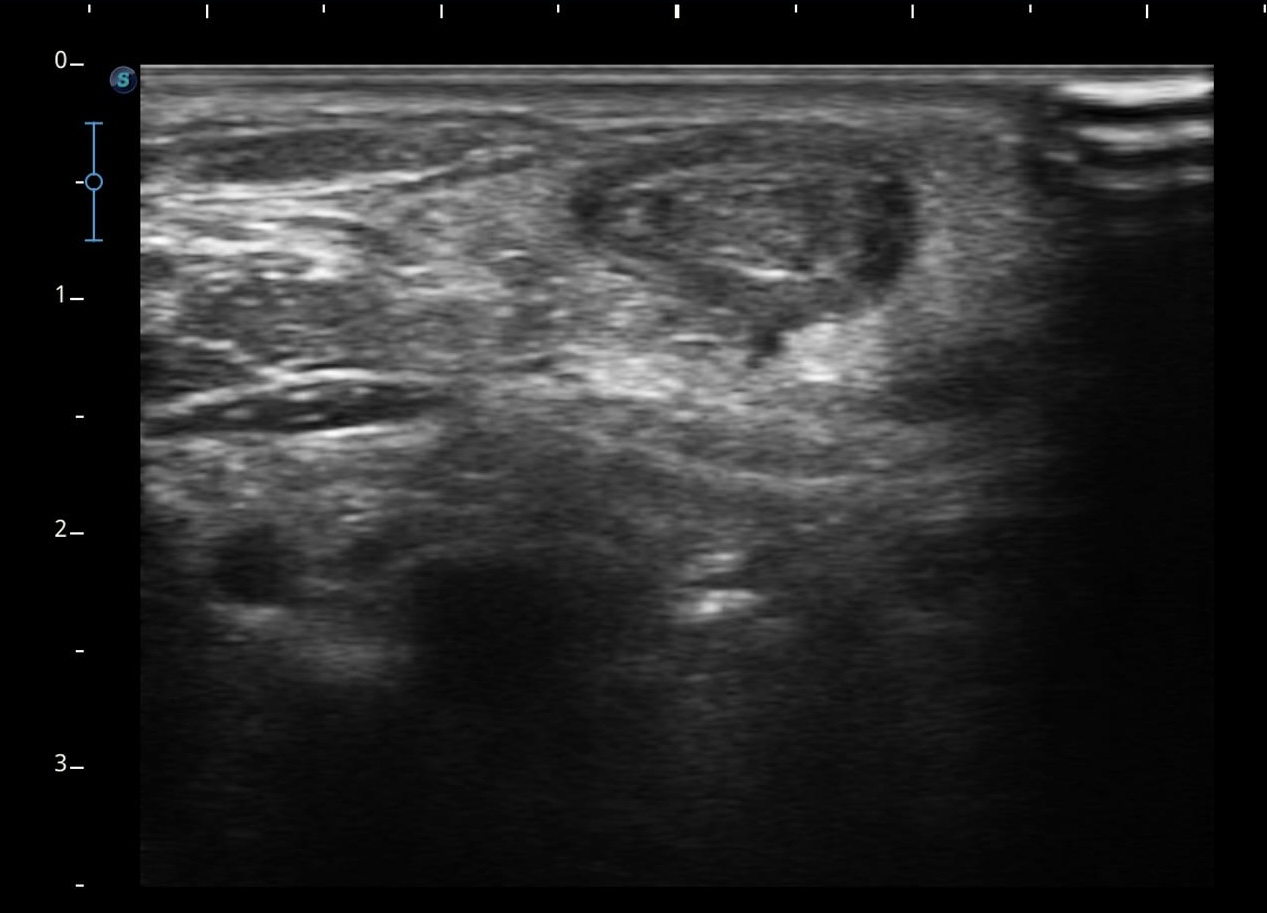

Se realiza ecografía clínica objetivándose ausencia de flujo en el interior de la luz, con imagen ecogénica en el interior compatible con trombo, no colapsándose a la presión con el transductor.

Sospechamos de trombosis venosa yugular externa (VYE). Se deriva a servicio de Urgencias para completar estudio.

Se realiza analítica de sangre (Dímero D 2029 ng/ml) y radiografía de tórax anodina. Se realiza eco-doppler cervical observándose trombosis de vena yugular externa izquierda al menos hasta su confluencia yugulosubclavia. Vena yugular izquierda no visualizada. Venas subclavia, axilar y braquiales izquierdas permeables sin datos de trombosis.

Se confirma nuestra sospecha diagnóstica: obstrucción total venosa central (OTVC) trombótica de la vena yugular externa.